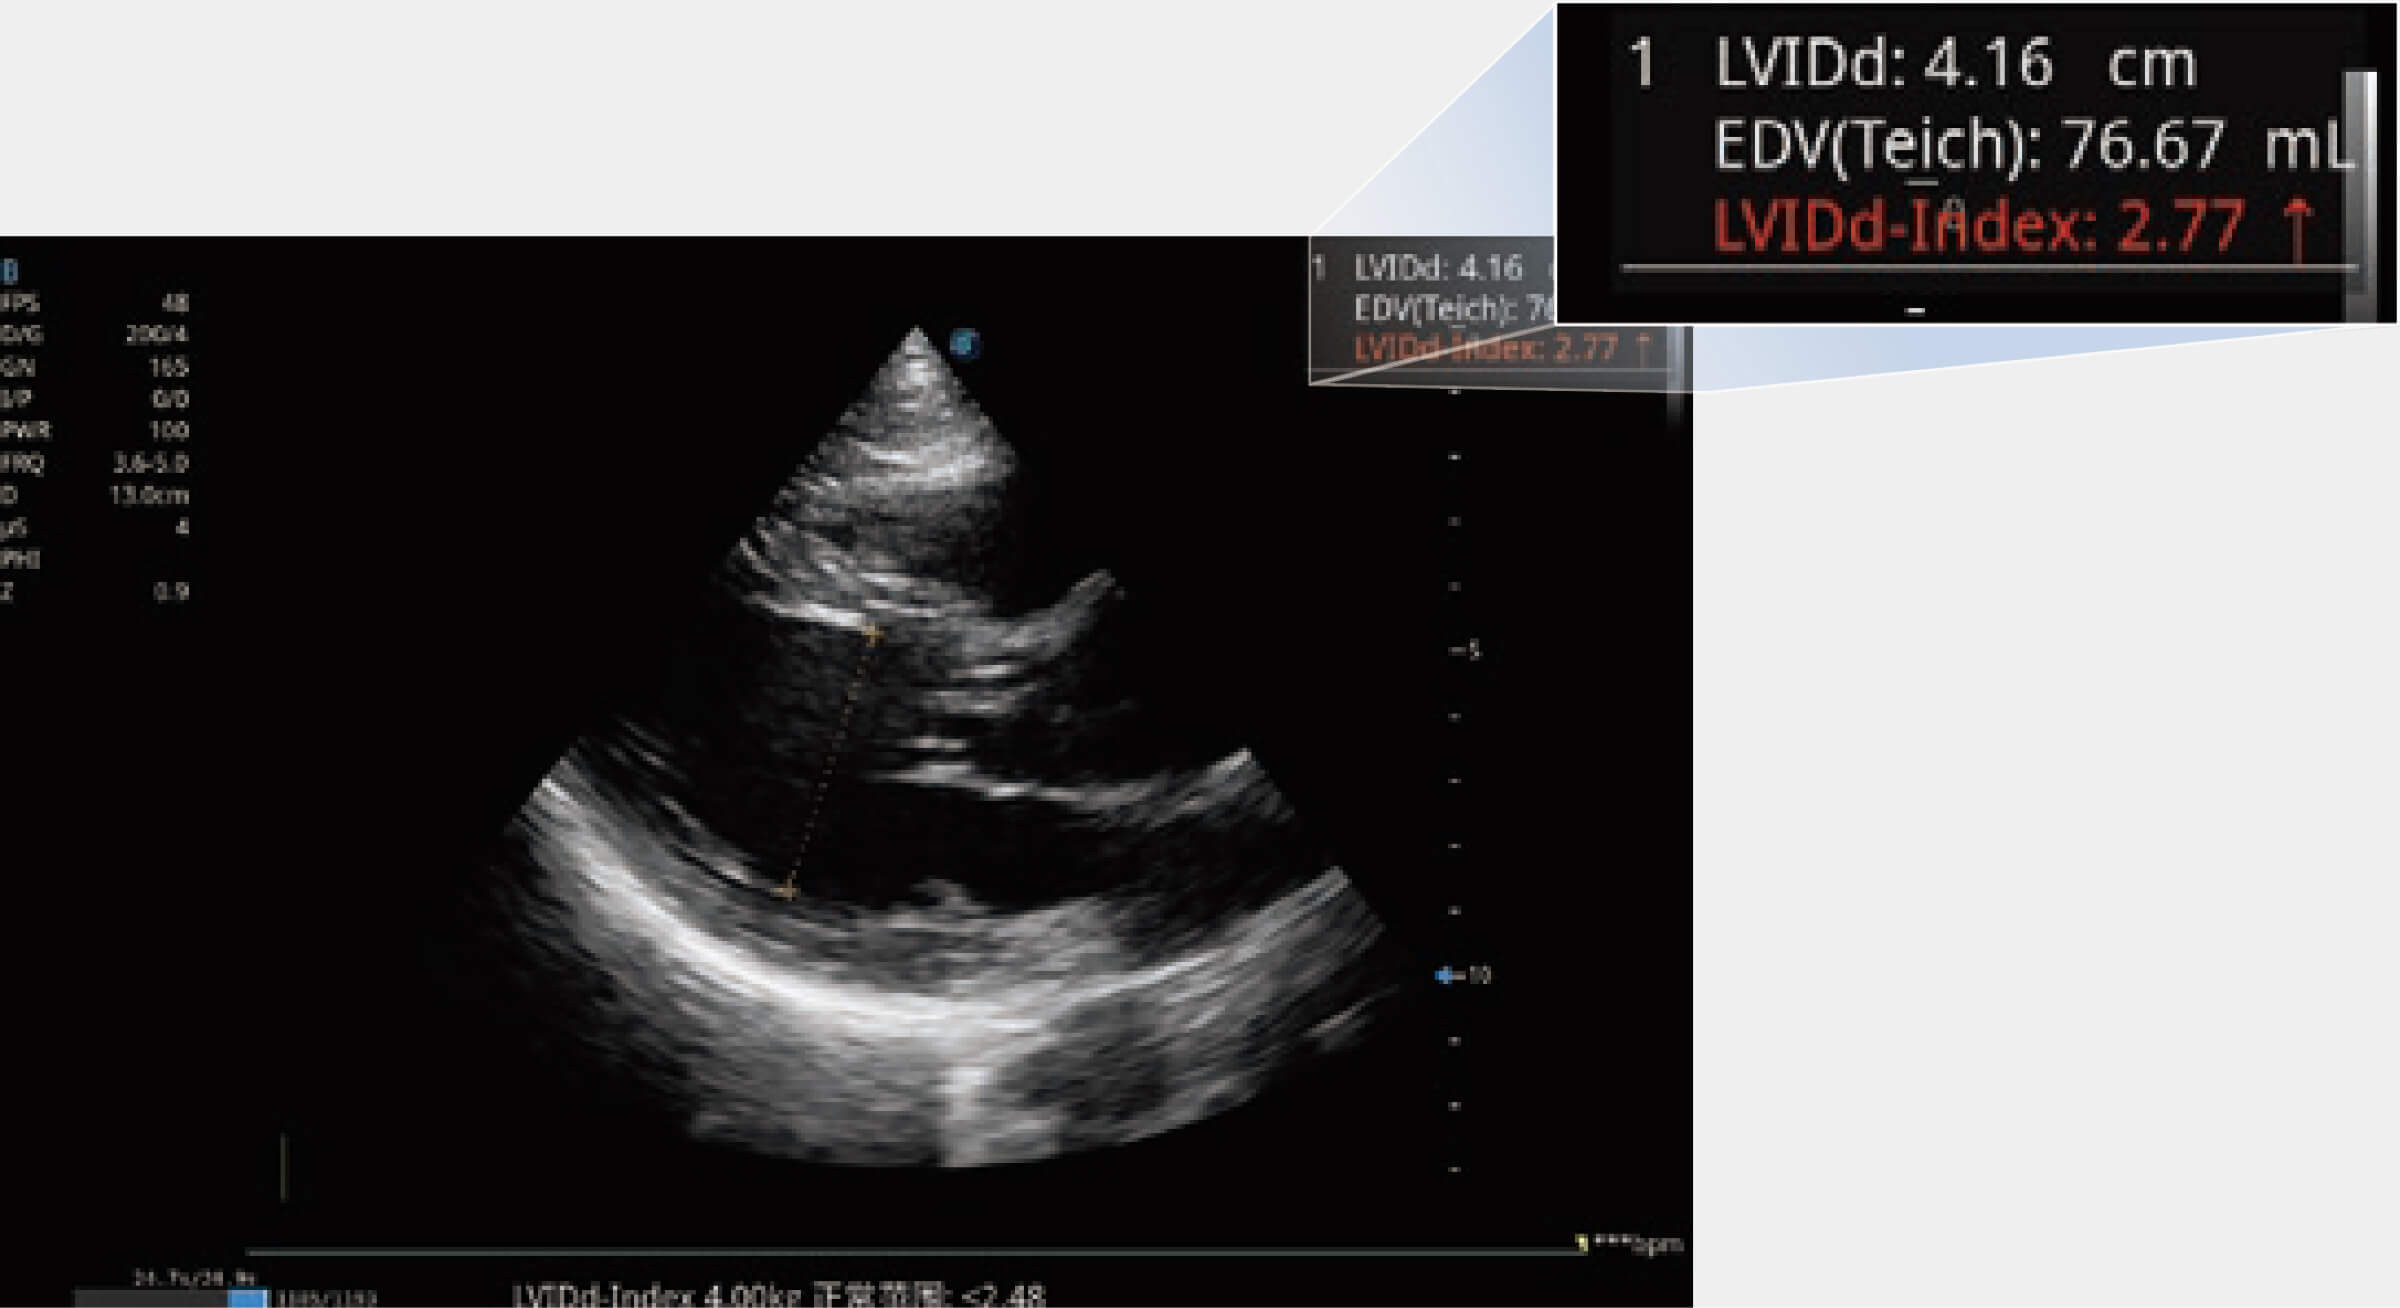

當(dāng)心臟測量結(jié)果超出正常范圍時(shí),可實(shí)時(shí)預(yù)警提示動物醫(yī)生,減少疾病漏診概率。

ProPet 70專為動物醫(yī)生設(shè)計(jì),對不同的動物體型和生理結(jié)構(gòu)作出了針對性的優(yōu)化。通過動物影像專用軟件,可滿足個(gè)性化的應(yīng)用需求,幫助動物醫(yī)生獲得更精確的診斷數(shù)據(jù)。

能夠基于左心室壁追蹤和辛普森法,自動計(jì)算射血分?jǐn)?shù),支持多個(gè)可移動點(diǎn)描跡,與手動測量相比,極大節(jié)省了動物醫(yī)生的時(shí)間和精力。